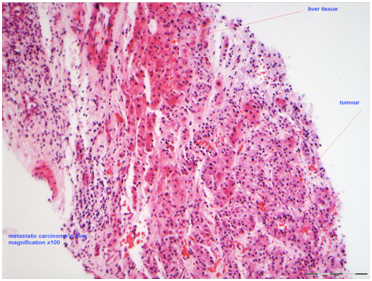

These patients are best served by a multidisciplinary approach involving Gynecologic oncologist, Uro-oncologist, dedicated histopathologists, radiologists and palliative care team [8].This case highlights the importance of bearing in mind the possibility of RCC in these patients, especially with proven histology (Figure 5&6), in order to optimize management to improve outcomes. If the patient is fit, a nephrectomy and excision of the metastases may be the best management options [8]. Due to multiple co-morbidities, our patient was not suitable for this and therefore, the aim of management was to achieve symptom control.

Figure 5: Histology showing metastatic carcinoma in the liver.